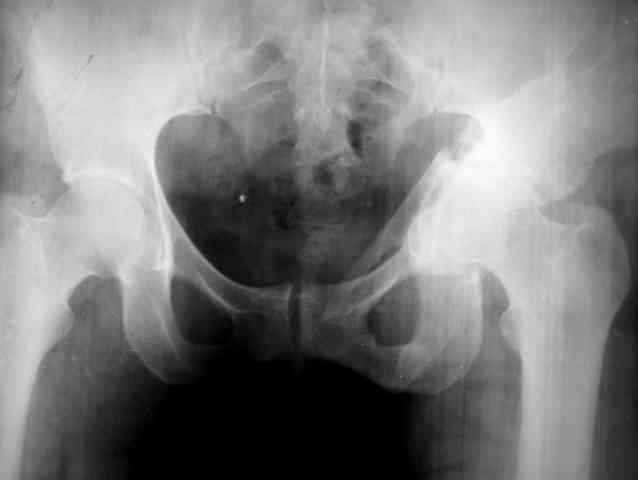

Псевдоартроз вертлужной впадины. |

Ув.коллеги,нужен совет по представленному случаю. Пациентка, 50лет. В 2003 году в результате дтп получила перелом вертлужной впадины.

1.5 месяца находилась на скелетном вытяжении, в дальнейшем до 10 месяцев после травмы ходила без опоры на конечность. Вернулась к труду, но в 2006 году перешла на инвалидность и была поставлена в областную очередь эндопротезирования. В данный момент уже находится в отделении, но, судя по рентгенограммам и данным КТ, сращения на уровне перелома не произошло. Что предпочесть?

1.Остеосинтез с костной пластикой и последующим эндопротезированием.

2."Октопус".

3.Кольцо Мюллера.

Заранее благодарен за ответы и ценные замечания.